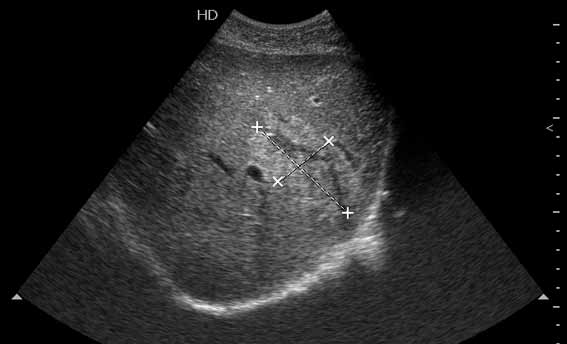

Разрыв печени у пациента 26 лет

Через трое суток